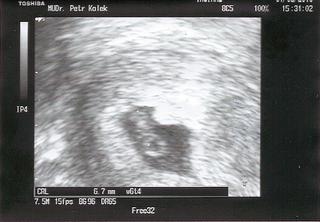

@suzane26 blahozelam krasna fazulka